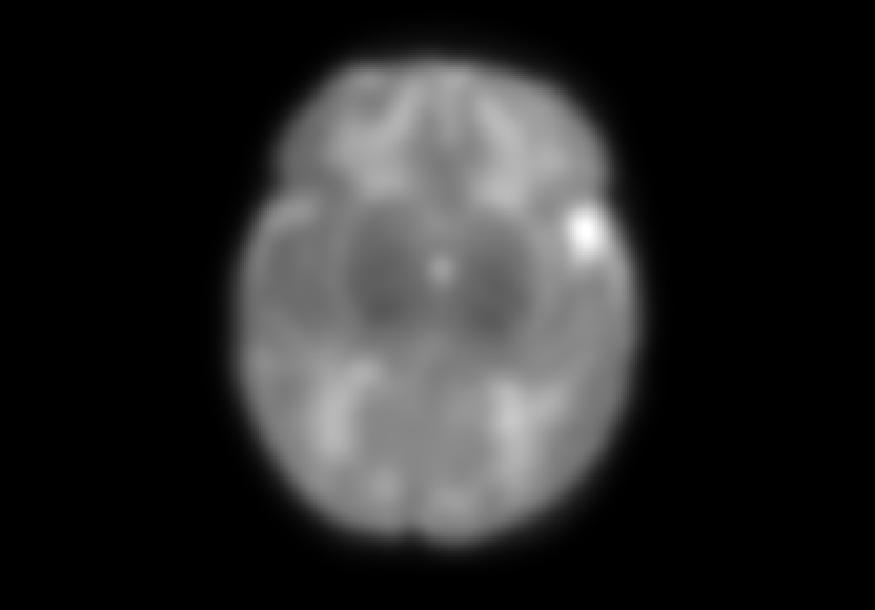

The dataset consisted of 70 3D T2-weighted brain MRI scans publicly available from the dHCP neonatal cohort. The segmentation maps had 10 classes, corresponding to: zero-pixel background, cerebrospinal fluid (CSF), cortical grey matter (cGM), white matter (WM), background bordering brain tissues, ventricles, cerebellum, deep grey matter (dGM), brainstem, and hippocampus. The scans covered an age range of 24.3-42.2 weeks. The data was available in NIfTI format; Figure 1 shows an example scan and corresponding tissue labels. We carried out a pre-processing step where each scan was independently normalised to zero-mean and unit-variance.